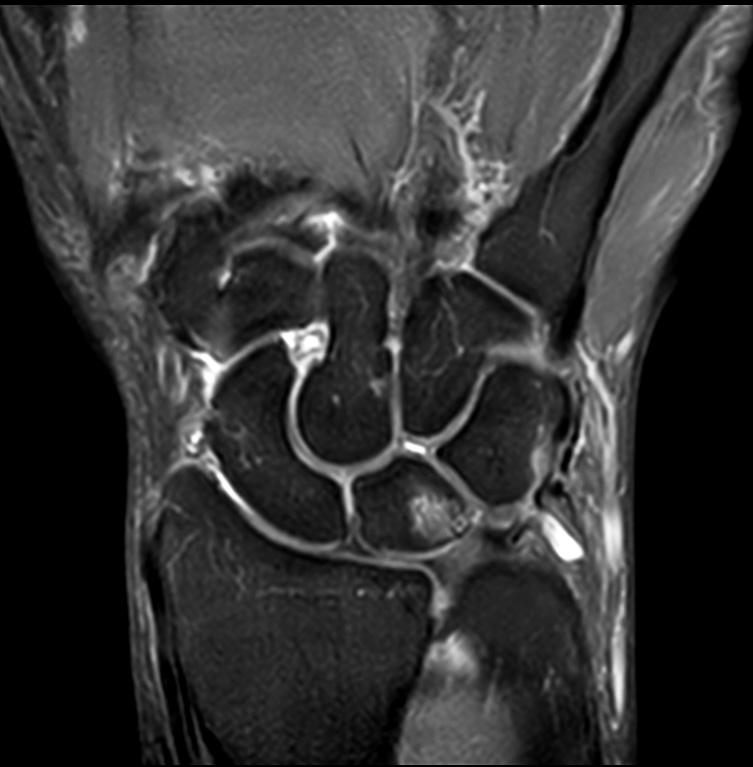

Comprehensive wrist imaging